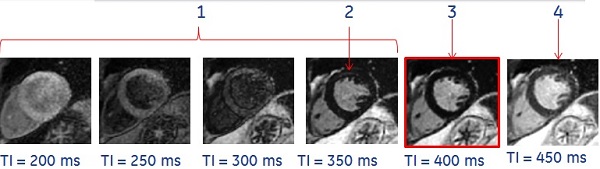

10. From the AutoView screen, review the images and note the TI time of each image. The Cine IR images provide an evolution of T1-contrast based on the TI time of each phase. Select the TI of the image that demonstrates the optimal myocardium contrast that can be used for the MDE scan.

Figure 1. Example of Cine IR images

Table 1. Image legend

NumberDescription

1TI is too short.

2Bounce point artifact.

3Optimal TI value.

4TI is too long.

• Note: the optimal inversion time (TI) that displays nulled normal myocardium signal. In the example above, the optimum TI is 400 ms. Use this TI time for the 2D MDE scan.

• Beware of the bounce point artifact, that indicates the TI is shorter than optimal. It is caused by signal cancellation at the tissue/blood interface. The bounce point artifact looks like a black outline along the endocardial and epicardial borders. Avoid this by choosing a higher TI.